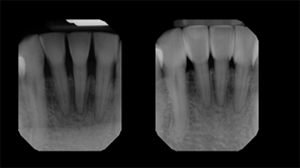

Fig. 12: Pre-operative (left) and post-operative (right) radiographs. The post-operative radiograph reveals the intimate adaptation and infinity edge margins that lend to the favorable tissue responses. Bioclear’s patented anatomic matrices enable predictable, atraumatic outcomes with subgingival contour changes unlike any other direct restorative methods.

Fig. 11 Fig. 12